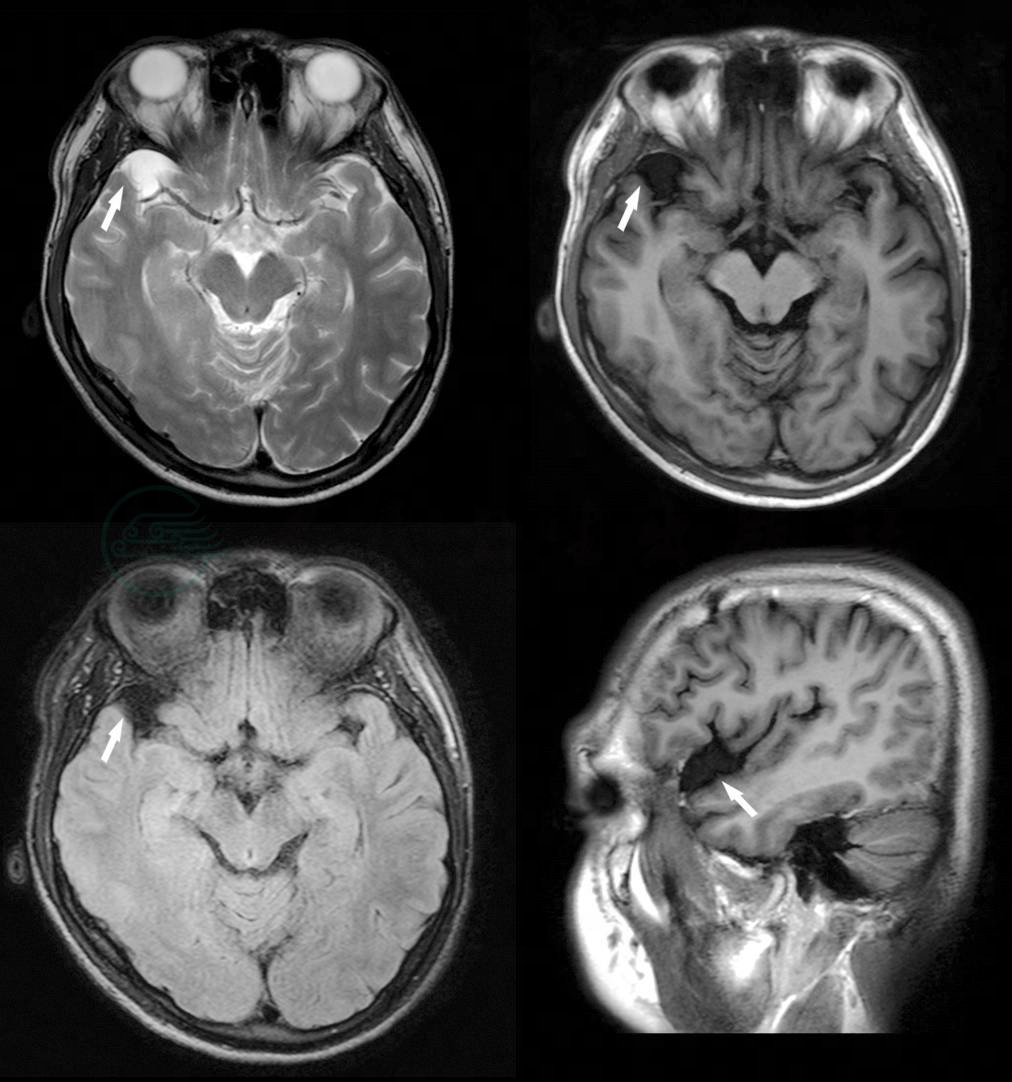

辅助检查:①三大常规、生化、甲状腺功能、催乳素、胸片、腹部彩超、心电图等检查未见明显异常。②脑电图“界限性脑电图:两半球基本波率为8~10Hz低-中幅α活动,以顶-枕区为主,双侧基本对称,调节、调幅较差,可见较多5~7Hz低-中幅波及活动,少量散在性低-中幅波,期间混杂较多低幅快波”。③头颅MRI检查提示:头颅形态大小如常,右颞部可见一囊状病变,大小约1.7cm×1.9cm×1.3cm,轻度占位效应,余脑实质内未见异常信号,侧脑室不对称稍扩大,余脑室、脑池、脑裂及脑沟对称,大小、形态正常,中线结构居中。脑干形态、信号未见异常。结果:颞部囊状病变,符合蛛网膜囊肿;脑室不对称扩大(图1)。

图1 右颞部蛛网膜囊肿